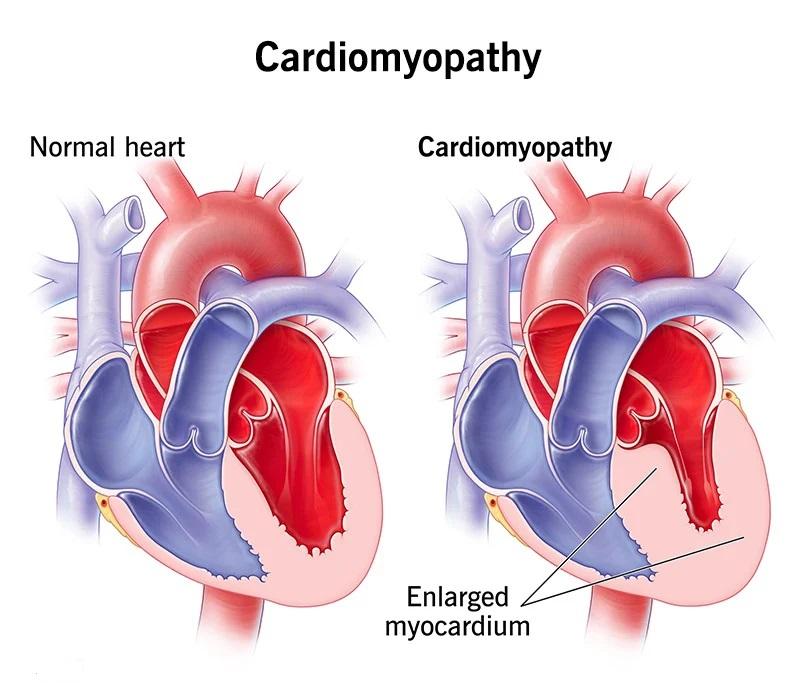

Cardiopatia ischemică se referă la un spectru de afecțiuni determinate de reducerea fluxului sanguin către mușchiul inimii, cel mai frecvent din cauza plăcilor de aterom care îngustează arterele coronare. Scăderea oxigenării miocardului poate genera simptome precum disconfort toracic sau lipsă de aer și poate evolua, în funcţie de gravitate, de la forme stabile până la sindroame coronariene acute; pe termen lung, afectarea repetată poate contribui la insuficiență cardiacă sau aritmii.

Procesele care stau la baza cardiopatiei ischemice sunt în principal legate de reducerea fluxului sanguin coronarian; ateroscleroza coronariană poate produce îngustări progresive ale arterelor și favorizează formarea placilor care pot ulceriza sau tromboza, reducând aportul de oxigen către mușchiul cardiac. În anumite situații, spasmul arterial sau disfuncţia microvasculară pot contribui la ischemie chiar în lipsa unor stenoze majore, iar dezechilibrele între cererea și oferta de oxigen (de exemplu în anemia severă sau la suprasolicitare) pot agrava tabloul clinic.